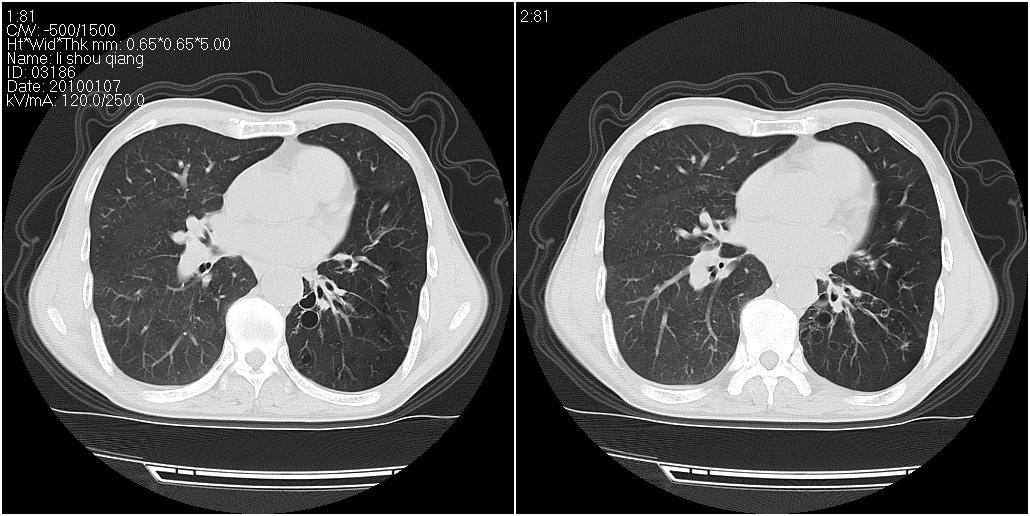

标题: CT24038:男性,58岁。主因咳嗽带血性CT检查。 [打印本页]

标题: CT24038:男性,58岁。主因咳嗽带血性CT检查。

右肺中叶外侧段见一不规则的软组织肿块,边缘可见毛刺,并见厚壁空洞,与胸膜分界欠清。另左下肺见多个小囊状扩张区

右肺中叶外侧段可见团块影,外形不规则,内见空泡征。左下肺见蜂窝状低密度透亮影,部分层面主动脉旁瘤样突出。考虑右肺中叶外围型肺癌可能性大,左下肺支气管扩张,主动脉弓瘤样突出。